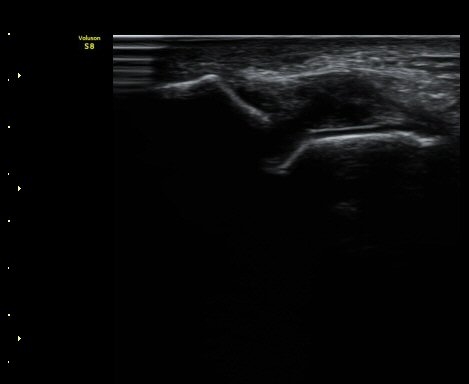

Àü°Å°ñºñ°ñÀδë Á¾´Ü¸é°Ë»ç¿¡¼­ ÀδëÀÇ ÀüÃþÆÄ¿­°ú ºÎÁ¾ÀÌ °üÂûµÈ´Ù(±×¸² 3, 4).

°ÇÃø(±×¸² 5)°ú ºñ±³ÇØ º¸¸é È¯ÃøÀÇ ÀÎ´ë ¼Õ»óÀÌ ¶Ñ·ÈÇÏ´Ù.